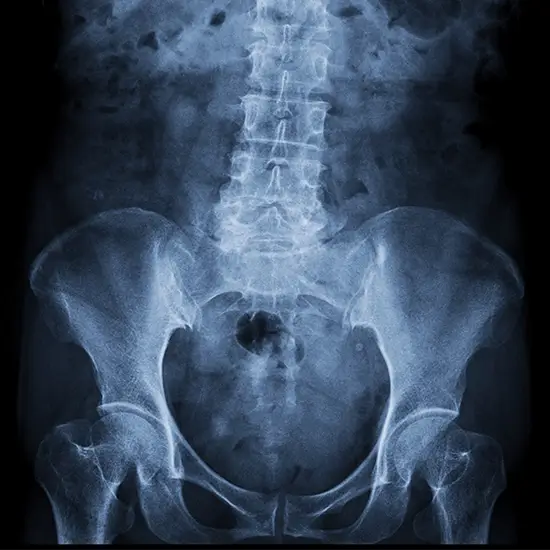

The LAT view of the right hip X-ray is used to examine the pelvis, the bones of the hip joint, and the soft tissues around it (skin and muscles).

The Right Hip Joint LAT View X-Ray detects any fractures of the bones that comprise the hip joint and tracks the bone's healing after it has been fixed. It identifies infection, osteoporosis, anomalies, uneven bone growth, osteoarthritis, and hip dislocation.